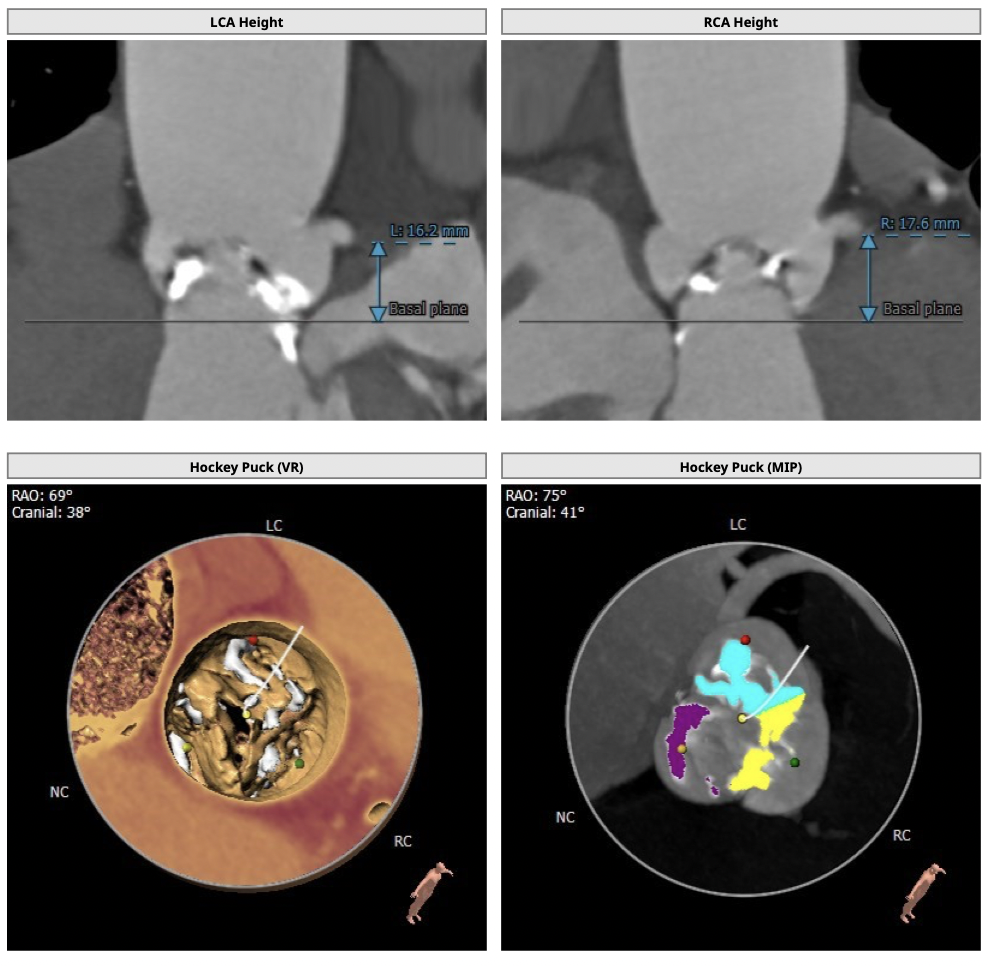

主动脉CT

图片

手术策略

难点分析:

*患者为TYPE0型二叶瓣,重度钙化(钙化积分高达1056),可见钙化延伸至左室流出道,瓣叶前交界缘存在粘连,瓣膜释放后发生瓣周漏的风险较高。

*患者为风湿性心脏病患者,瓣膜释放后移位风险增加,对术者瓣膜植入位置的操控要求较高。

制定策略:

经分析研判,拟从右侧股动脉穿刺入路,使用18mm球囊预扩,采取downsize手术策略,选用L23号的VenusA-Valve瓣膜,因患者伴有风湿性心脏病,瓣膜容易移位,故采用VenusA-Plus可回收输送系统确保瓣膜的稳定释放,瓣膜释放后结合造影和超声情况,决定是否后扩。